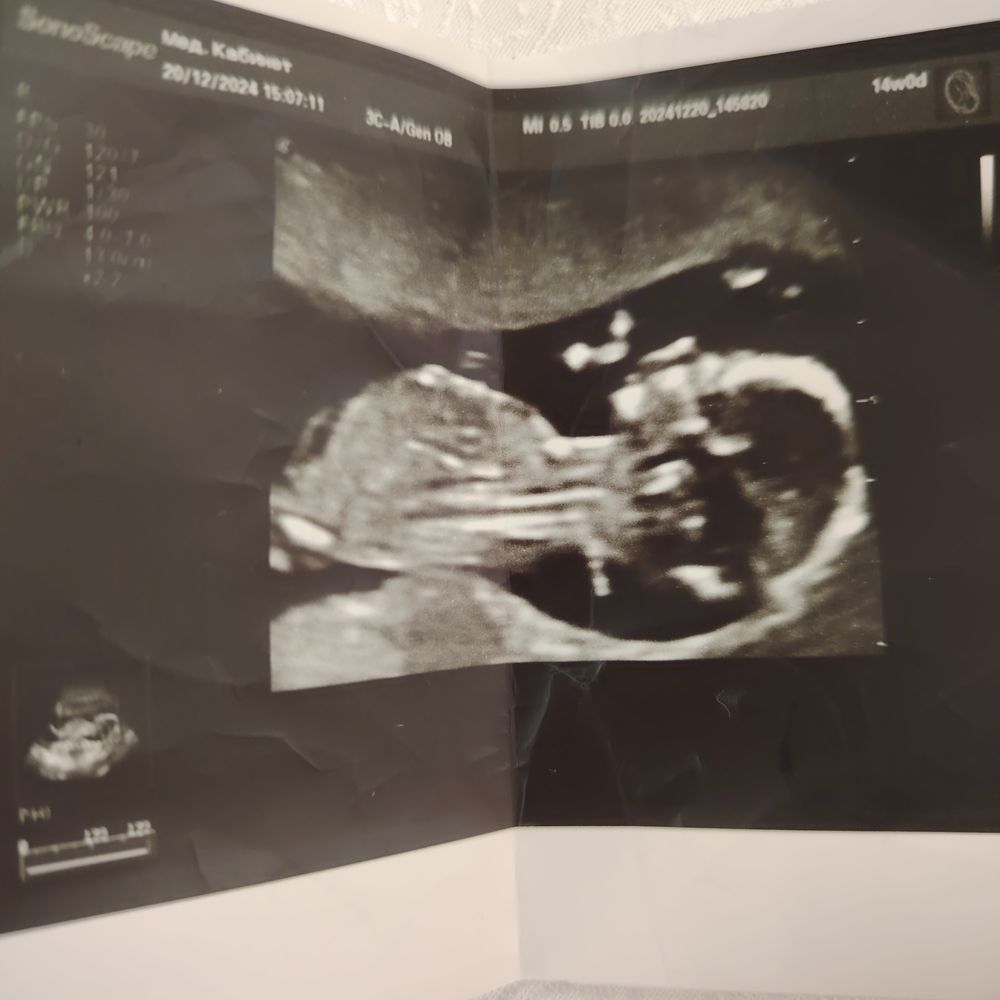

Валерия , Изображение Изображение Изображениевот ещё так есть)

Ирина Качанова, похоже яйки)😂 У моей булочку сразу выдано было , сама в монитор увидела

Посмотрела ваши снимки ниже - мне кааааажется, что мальчик